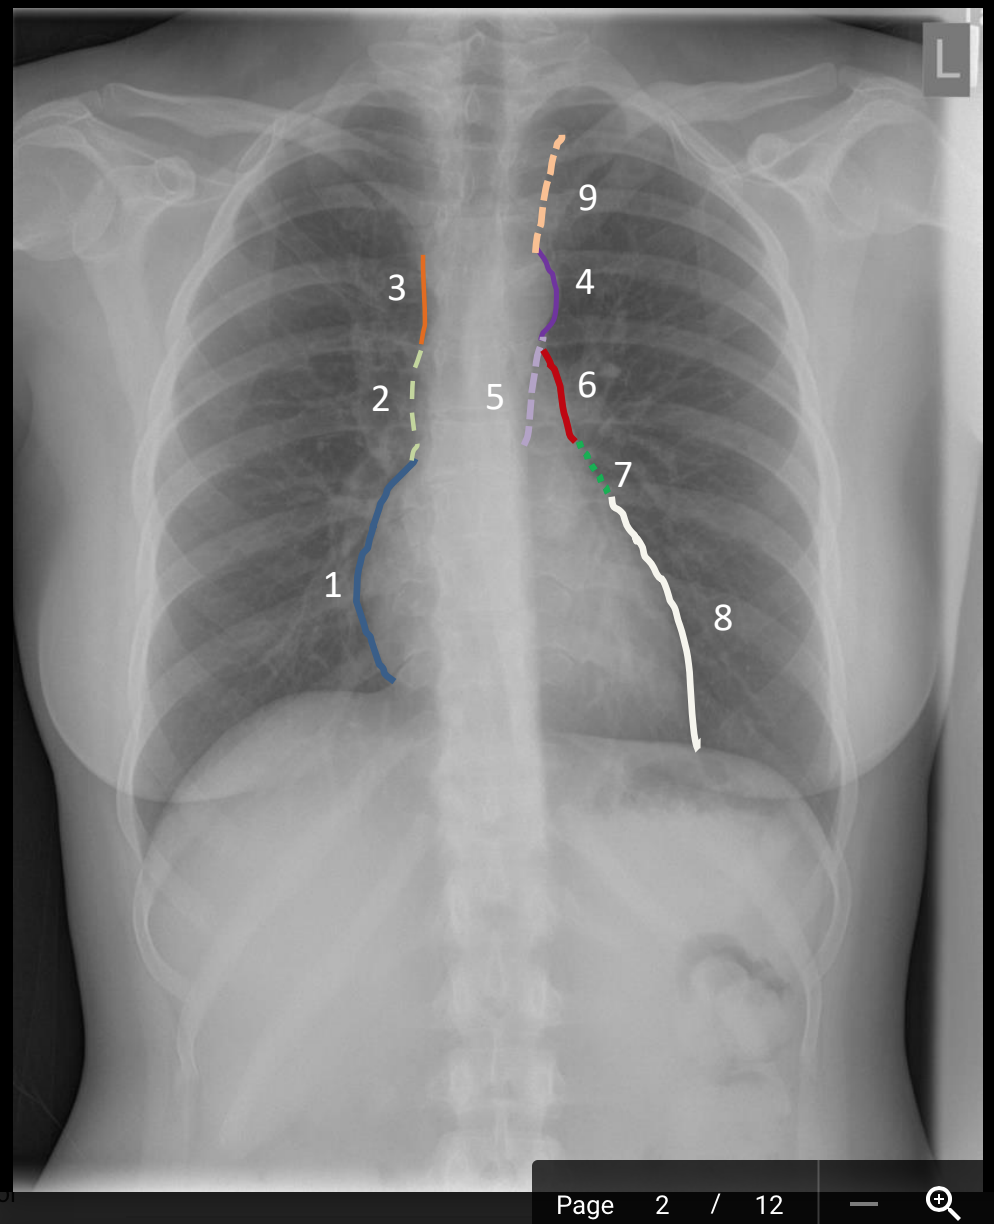

what is the blue outline?

mediastinal shadow

What is 9?

possibly common carotid a. or internal jugular v.

What is 8?

left ventricle

What is 7?

left atrial appendage (auricle)

What is 6?

pulmonary trunk

What is 5?

descending thoracic aorta

What is 4?

aortic knob/knucle (arch)

What is 3?

superior vena cava

What is 2?

ascending aorta/superior vena cava

What is 1?

right atrium